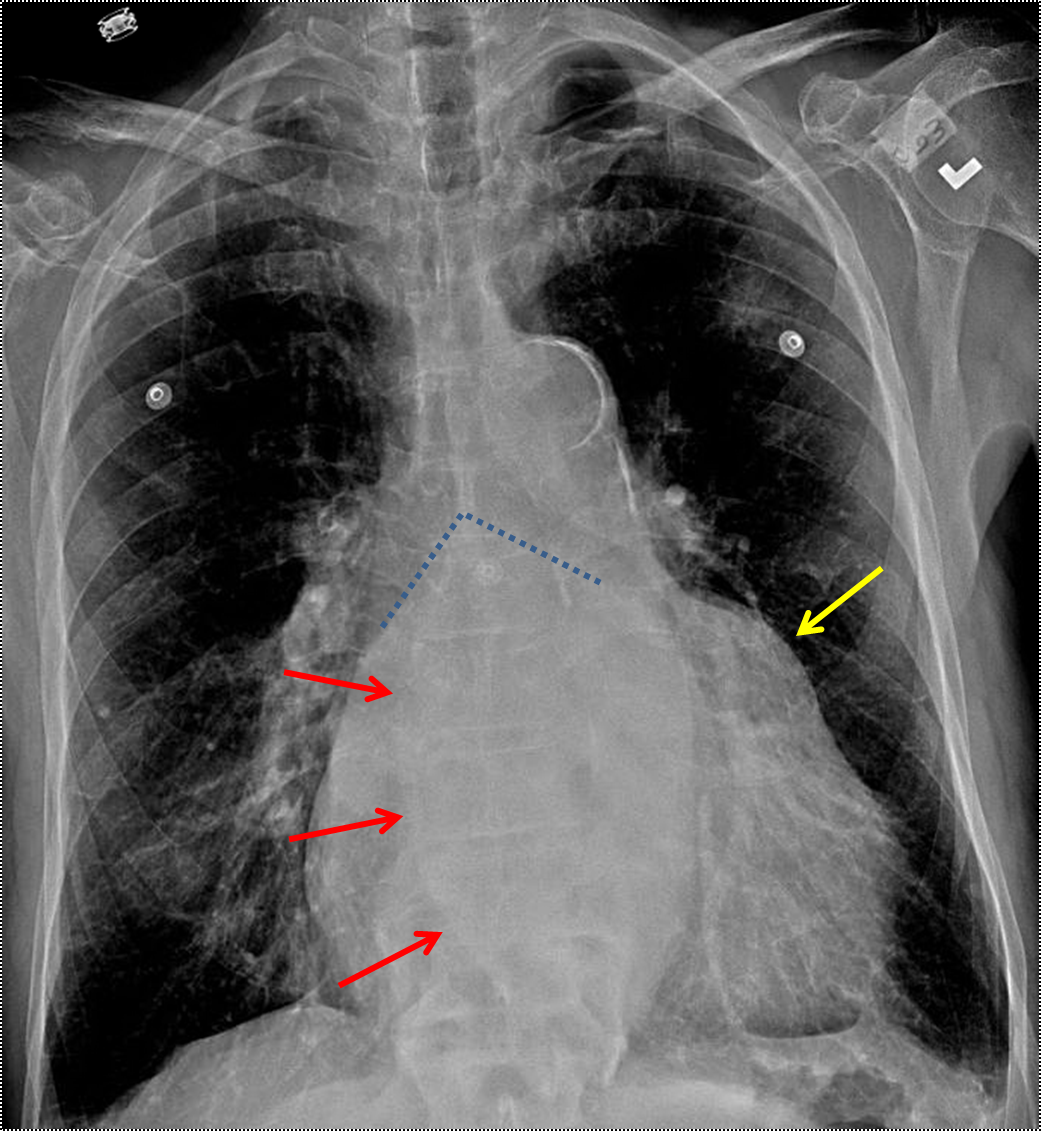

Bulging left atrial appendage (yellow arrow). Splaying of the carina (blue dotted lines). Double density sign (red arrows). CT confirms marked left atrial enlargement (red arrows).